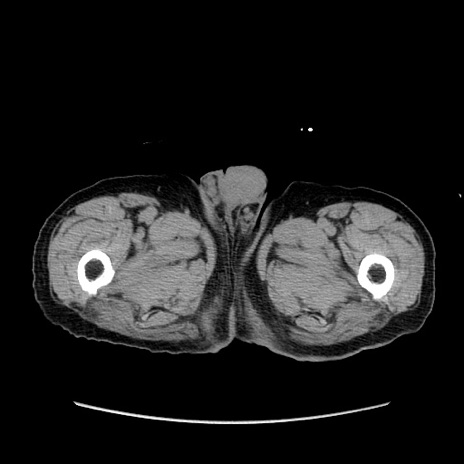

症例24(横断像)

【症例】80歳代男性

【主訴】左側腹部痛、嘔吐

【現病歴】本日早朝より左腹部に痛みあり。昼頃嘔吐認めたため、救急要請。

【既往歴】直腸癌(Mile手術)、胆摘

【身体所見】意識清明、BT 35.9℃、BP 221/93mmHg、SpO2 97%(RA) 、腹部:左ストーマ周囲に限局性の腹部膨隆あり。 膨隆部自発痛・圧痛あり・軟。

【データ】WBC 7700、CRP 0.09